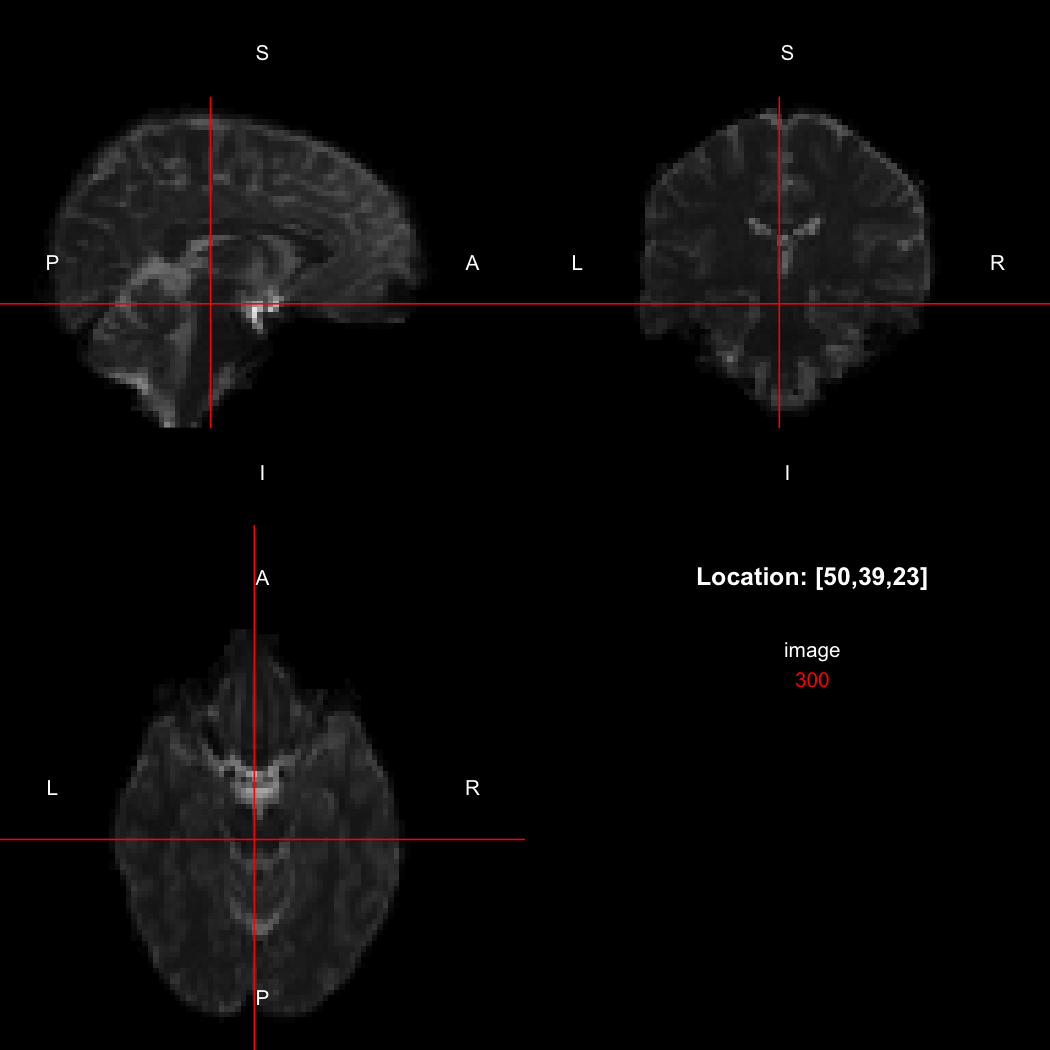

The package contains a basic image viewer, which can be used interactively or noninteractively to examine 2D or 3D images.

view(image)

plot of chunk unnamed-chunk-5

By default, the viewer shows labels indicating image orientation, crosshairs pinpointing the currently selected location, the numerical indices of the current location, and the value of the image at that location. Options allow each of these to be turned off, for the content of the bottom-right panel to be customised entirely, for the colour scale to be changed, and for additional images to be layered on top of the base image. See ?view for details.

So, here, “LAS” means that the positive x-axis points left, the positive y-axis anterior and the positive z-axis superior. This is the so-called “radiological” orientation convention, and can be requested when viewing images for those who are used to it:

view(image, radiological=TRUE)

plot of chunk unnamed-chunk-12

Notice the left (L) and right (R) labels, relative to the view shown above. Setting the radiologicalView option to TRUE will make this the default for all future views.